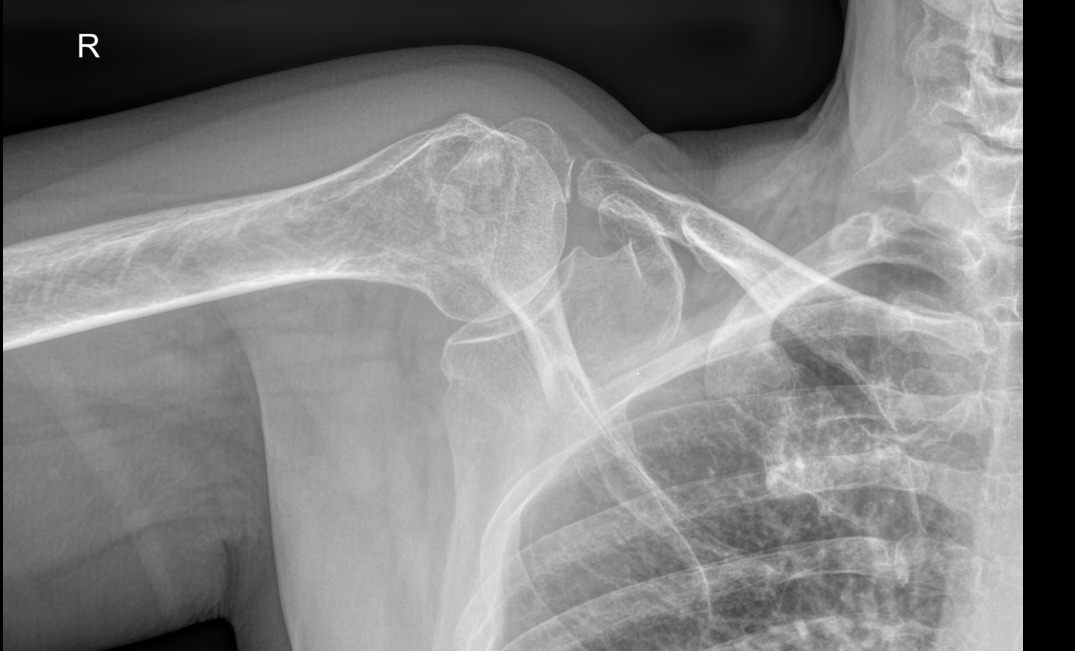

Рентгенография относится к стандартным методам диагностики плечевых суставов. На снимке можно обнаружить все патологические изменения, произошедшие в данной области, а также стадии болезни. Рентген используется также для выбора метода лечения и его контроля. Рентгеновское оборудование последнего поколения позволяет делать серию снимков с минимальной дозой облучения. Это важно, так как дает возможность выполнить необходимое количество снимков в динамике.

Снимки выполняются в разных проекциях, в зависимости от того, какой элемент сустава требуется визуализировать.

• Костно-травматические изменения ― переломы, вывихи, остеофиты;

• Состояние суставных поверхностей ― не нарушено, эрозии;

• Суставные щели ― сужение, обызвествление капсулы, наличие выпота;

• Изменения в костных тканях ― изменений нет или наблюдаются разные патологии;

• Изменения в мягких тканях ― отечность, инородные тела;

• Новообразования любой природы.